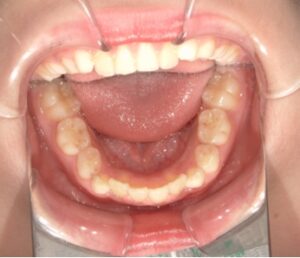

toshisika_case_after_No2_5